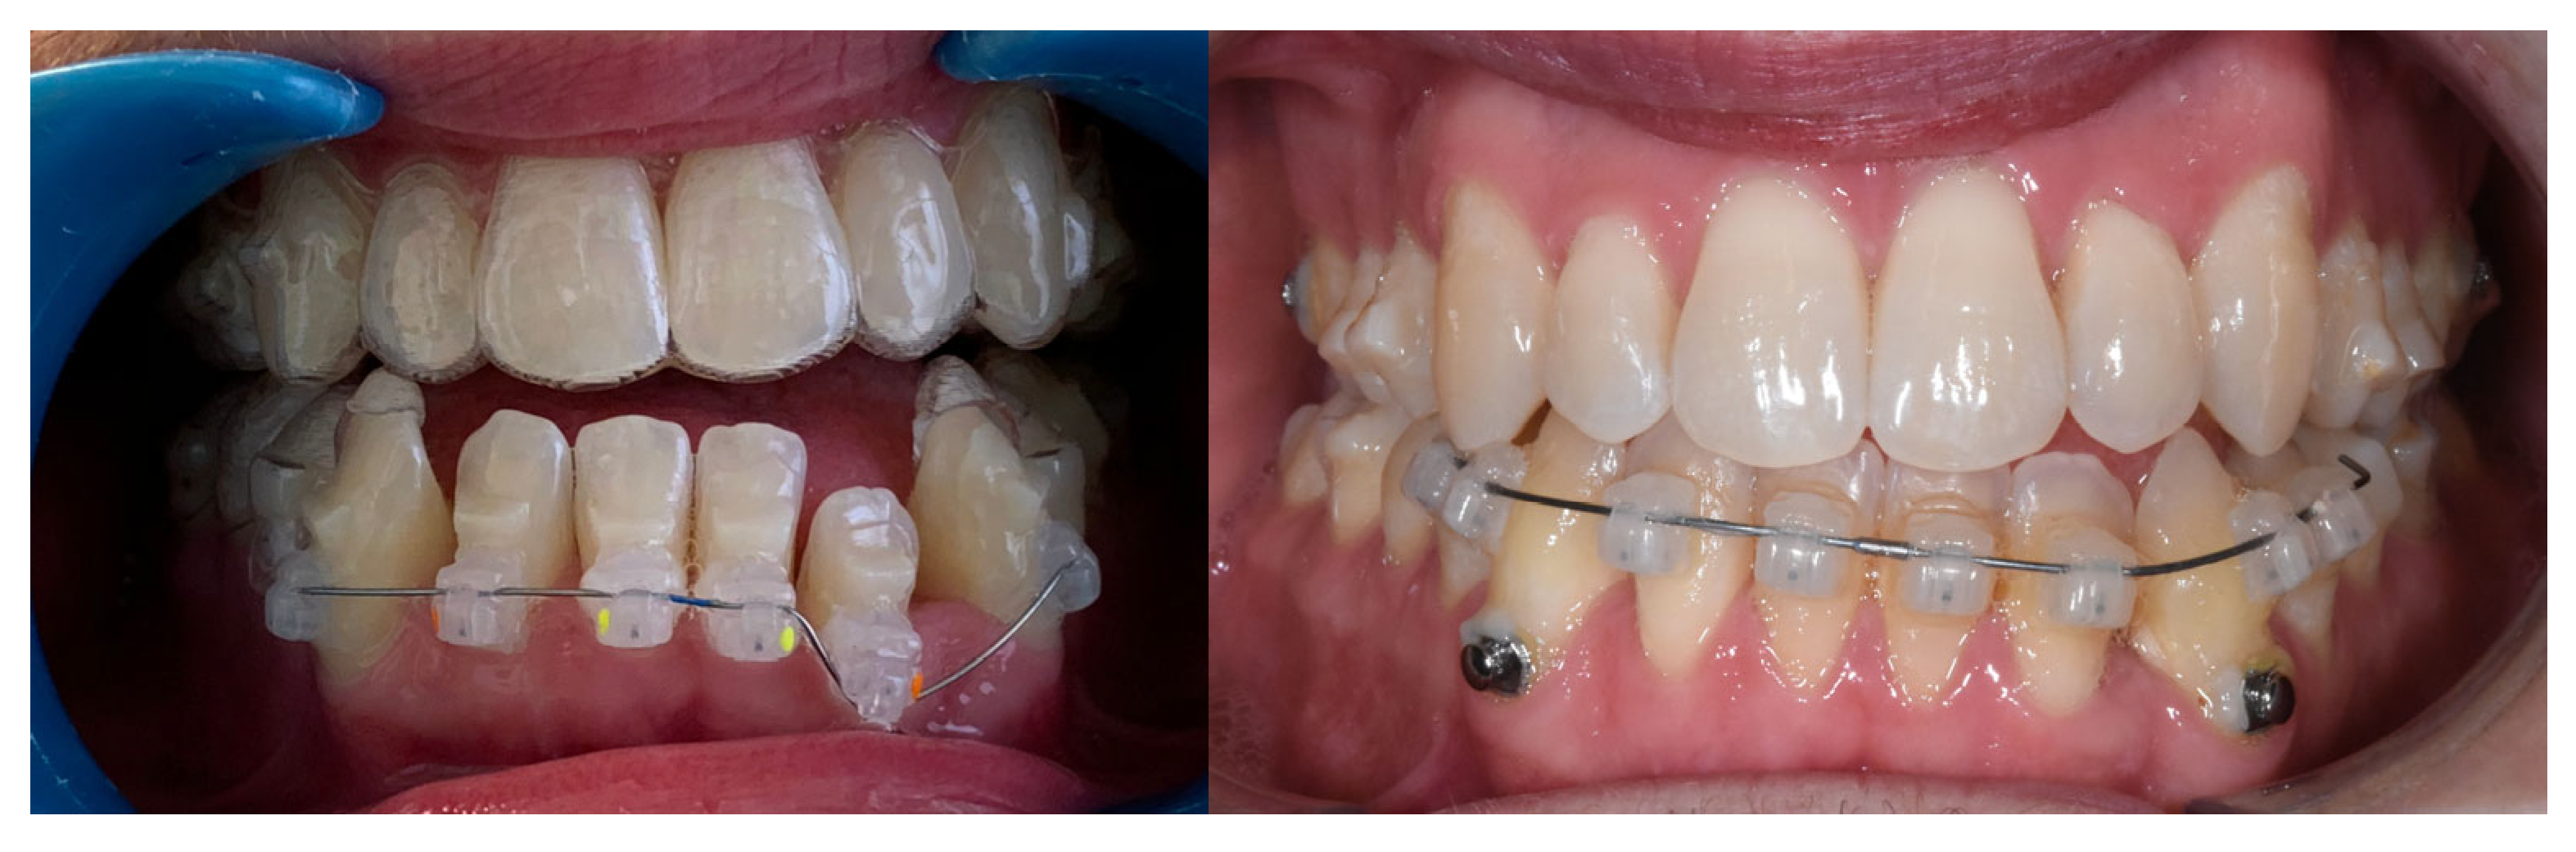

2.3. Treatment Progress

Treatment began with the extraction of the upper right second molar, performed by the referring general dentist. Once the Carriere® Motion appliances were bonded from the lower right first premolar to the lower right second molar and from the lower left first premolar to the lower left first molar, and the maxillary Invisalign® aligners were in place, the first phase of Class III intermaxillary elastics was initiated using ¼″, 6 oz elastics for one month, then intensified with 3/16″, 8 oz elastics (Figure 2). Achievement of a bilateral Class I molar relationship marked the transition to the second phase of treatment (Figure 3).

Figure 2. Intraoral view of the Carriere® Motion 3D Class III appliance during the sagittal correction phase.